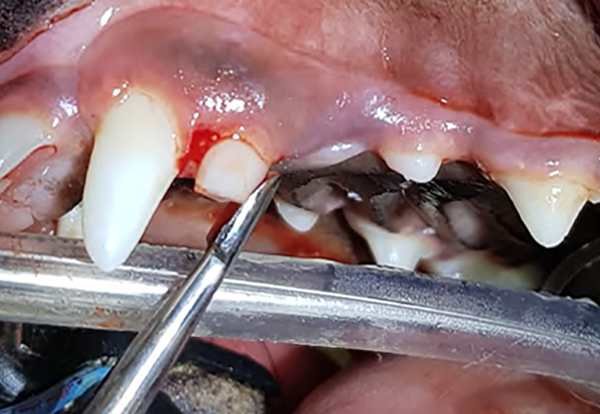

Figure 3A : Persistance de la canine déciduale maxillaire G chez un Teckel de 8 mois. L’extraction est indiquée à partir du moment où la dent définitive a entamé son éruption et que la dent déciduale n’a pas de mobilité afin d’éviter des problèmes de

malocclusion et d’encombrement dentaire.

Figure 3B : Radiographie intra-orale montrant la longueur, la courbure et la finesse de la racine de la canine déciduale maxillaire G pouvant rendre l’extraction de cette dent délicate. Une extraction chirurgicale (lambeau, alvéolotomie) peut être nécessaire.

Figure 3C : La courbure de la dent rend difficile le passage du luxateur le long de la face distale (arrière) de sa racine. Afin de faciliter le travail du luxateur sur la face distale, il est possible de sectionner la couronne et ainsi limiter la gêne liée

à la courbure de la dent.